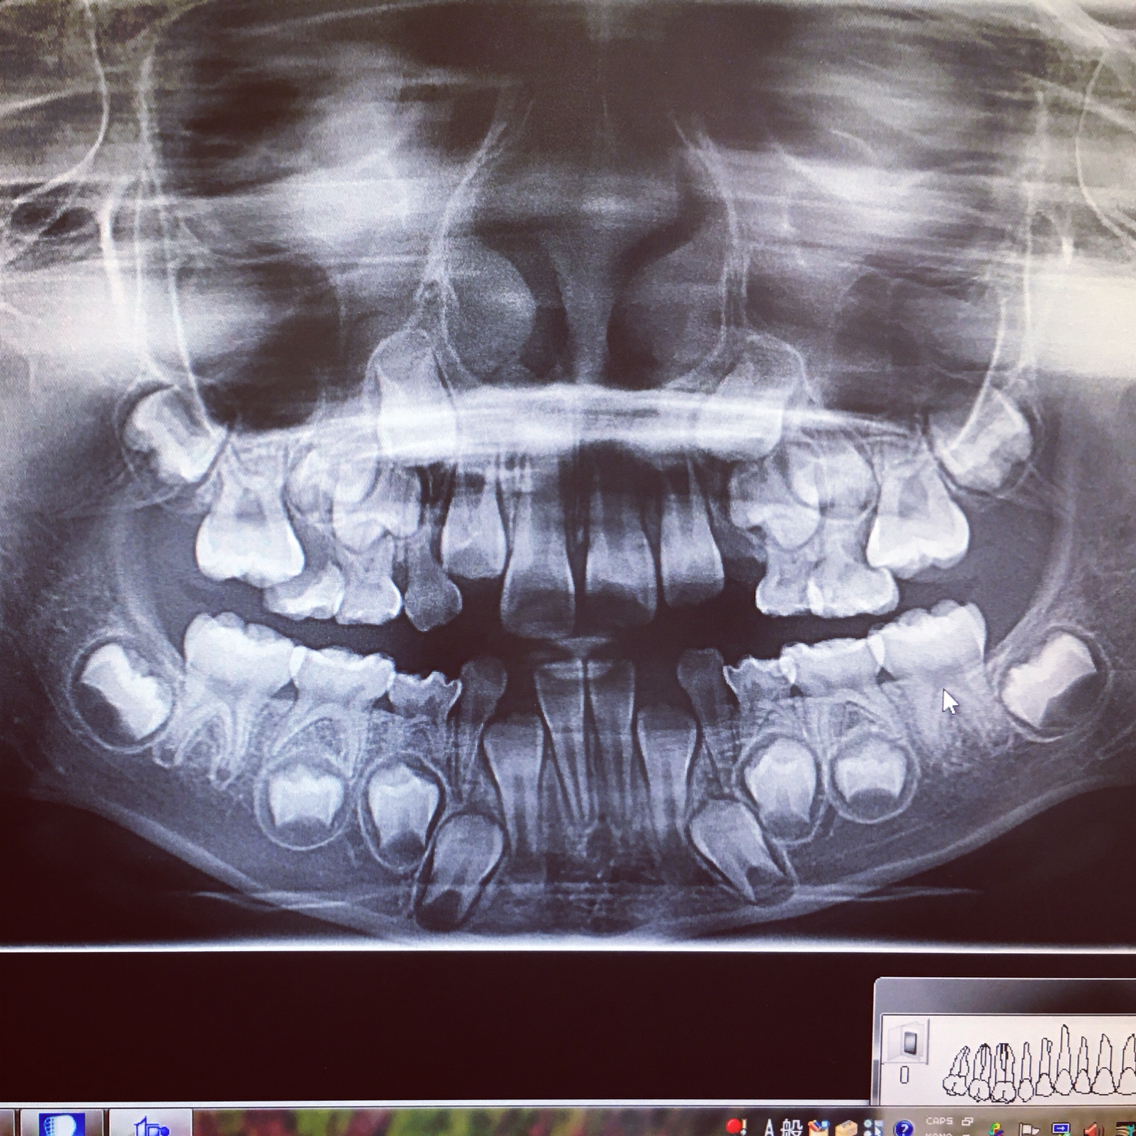

歯抜けメー。7歳ですでに10本抜けました…

レントゲンを撮ってみたら…

うじゃうじゃある歯に驚愕┌( ಠ_ಠ)┘

人体の神秘です…(ー ー;)